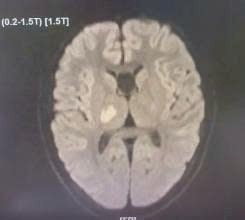

Ngày 13/9, Bệnh viện Nhi Thái Bình tiếp nhận một bệnh nhi nam 13 tuổi trong tình trạng đặc biệt. Em vốn khỏe mạnh nhưng bất ngờ xuất hiện yếu và tê bì nửa người trái, đi lại khó khăn.

Khi nhập viện, trẻ tỉnh táo, không sốt, không co giật, song vận động và cảm giác nửa người bị suy giảm rõ rệt. Từ những biểu hiện này, các bác sĩ chẩn đoán nhiều đến khả năng đột quỵ não ở trẻ em, một tình trạng nguy hiểm nhưng dễ bị bỏ sót bởi lâu nay phần lớn mọi người thường chỉ nghe và biết đến đột quỵ như một căn bệnh của người già.